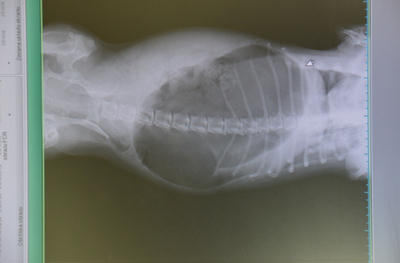

Skręt żołądka.